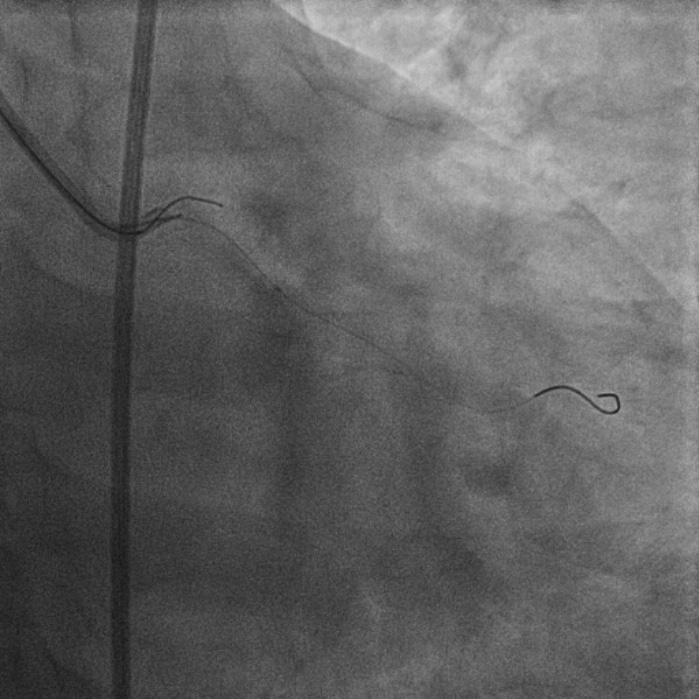

8F JL coronary guide catheter was taken from the right femoral artery and a TIG diagnostic catheter was taken from right radial artery and bilateral angiograms were taken. A floppy guide wire was placed in Lcx and ostial Lcx lesion was predicated with a 2*12 mm non compliant balloon. An IVUS catheter was placed over Lcx wire and under IVUS guidance a Gaia 3 coronary wire (Asahi, Japan) over a micro catheter was used to probe the ambiguous osmium of LAD (T1). Using contralateral injection in RCA, the Gaia 3 wire was seen extending into the false lumen in distal LAD. A Conquest Pro 12 (Asahi, Japan) was then taken over a micro catheter using a parallel wire strategy and successfully negotiated in distal true lumen of LAD (T2). After pre dilatation of LAD, Conquest Pro wire was exchanged for a floppy guide wire over a micro-catheter. IVUS run was then taken from LAD to LM and LCx to LM for vessel sizing. In view of the discrepancy in size of LAD/LCx and LM, 2 coronary stents were placed in a V technique from LM to LAD and LM to LCx and deployed. The stents were then post dilated and final kissing balloon inflation was done and the results were optimised by IVUS. Final cine showed well expanded LM LAD/LCx stents with TIMI 3 flow (T3).